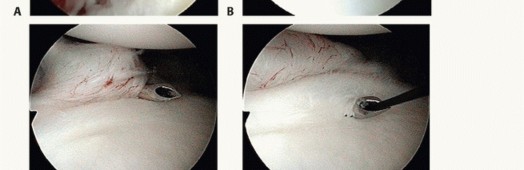

We begin with a standard posterior viewing portal, established approximately 2 cm inferior and 1 cm medial to the posterolateral acromial angle. A thorough, systematic diagnostic sweep is performed. We meticulously document the integrity of the biceps anchor (assessing for SLAP tears), the articular surface of the rotator cuff, the bare area of the humeral head, and the entire 360-degree labral circumference. We specifically probe the anteroinferior labrum to assess the extent of the Bankart detachment and evaluate the volume and patulousness of the axillary pouch.

Image

The establishment of the anterior working portals is arguably the most critical step of the setup; poor portal placement condemns the surgeon to a difficult, compromised repair. Utilizing an outside-in spinal needle localization technique, an anterosuperior portal is created high in the rotator interval, just anterior to the biceps tendon. This serves primarily as a viewing portal for the inferior work and for suture management. The anteroinferior (5 o'clock) portal is then established just superior to the subscapularis tendon. This portal must be placed low enough to allow a 45-degree "deadman's angle" approach to the 5:30 position on the glenoid rim for the foundational inferior anchor.